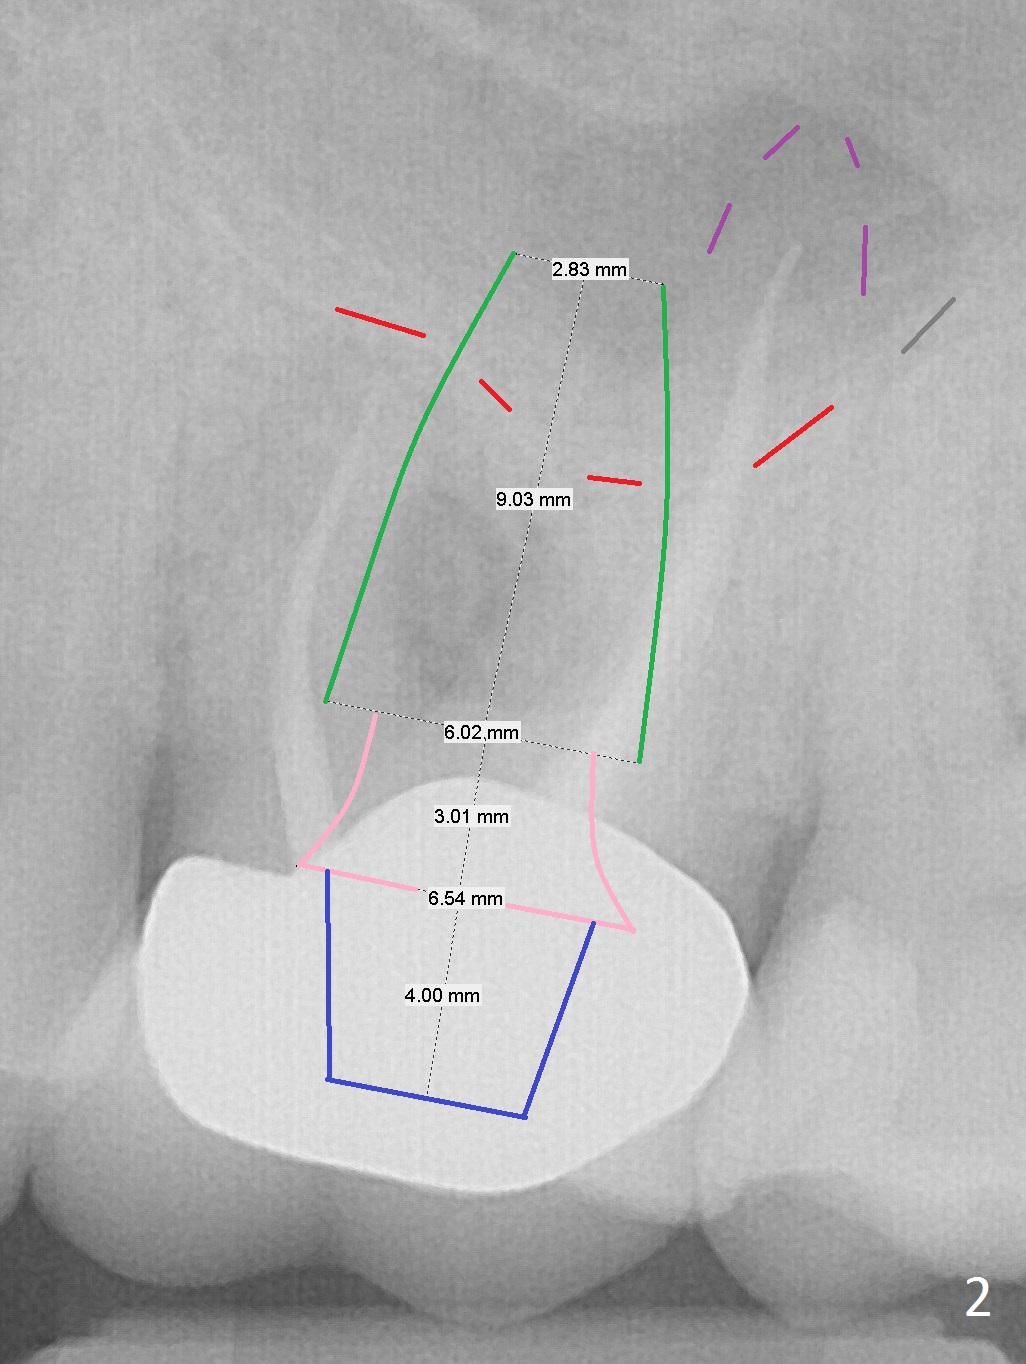

A 70-year-old man will return for #14 extraction and implant placement after consultation with an endodontist (Fig.1). Note the large periapical radiolucencies associated with the mesiobuccal and palatal roots (*). After extraction and Metronidazole, start osteotomy in the septum, place PRF membranes/plug and allograft/Osteogen and then a dummy implant or tap. Place a large definitive implant (Fig.2 green) higher than the sinus floor (red), but lower than the palatal apex (purple).